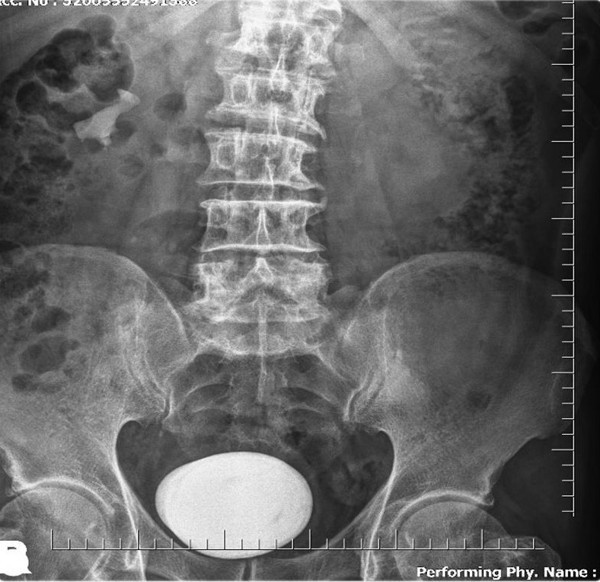

ORDU’nun Fatsa ilçesinde idrar yolu enfeksiyonu bulunan hastanın mesanesinden büyük boy patates yumrusu kadar taş çıkarıldı.

Abone olSürekli idrar yolu enfeksiyonu olan ve dayanılmaz idrar yanması, sık idrara çıkma ve idrar tutmakta zorlanması olan hasta ilaç tedavilerinden fayda görmemesi üzerine Fatsa Devlet Hastanesi Üroloji Polikliniği de Opr. Dr Yüksel Şahin’e başvurdu. Yapılan tetkik ve tahliller sonucunda hastanın mesanesinde çok büyük bir taş saptandı.

Literatürde bu boyda taş görülmesi çok nadir karşılanırken hastanın mesanesinden çıkan taş şaşkınlıkla karşılandı. Derhal ameliyata alınan hastanın mesanesindeki taş kapalı yöntemle çıkarılması mümkün olmadığından açık sistolitotomi ameliyatı yapıldı. Herkesi şaşkına çeviren büyük bir patates yumrusu şeklindeki taş başarılı şekilde alındı.